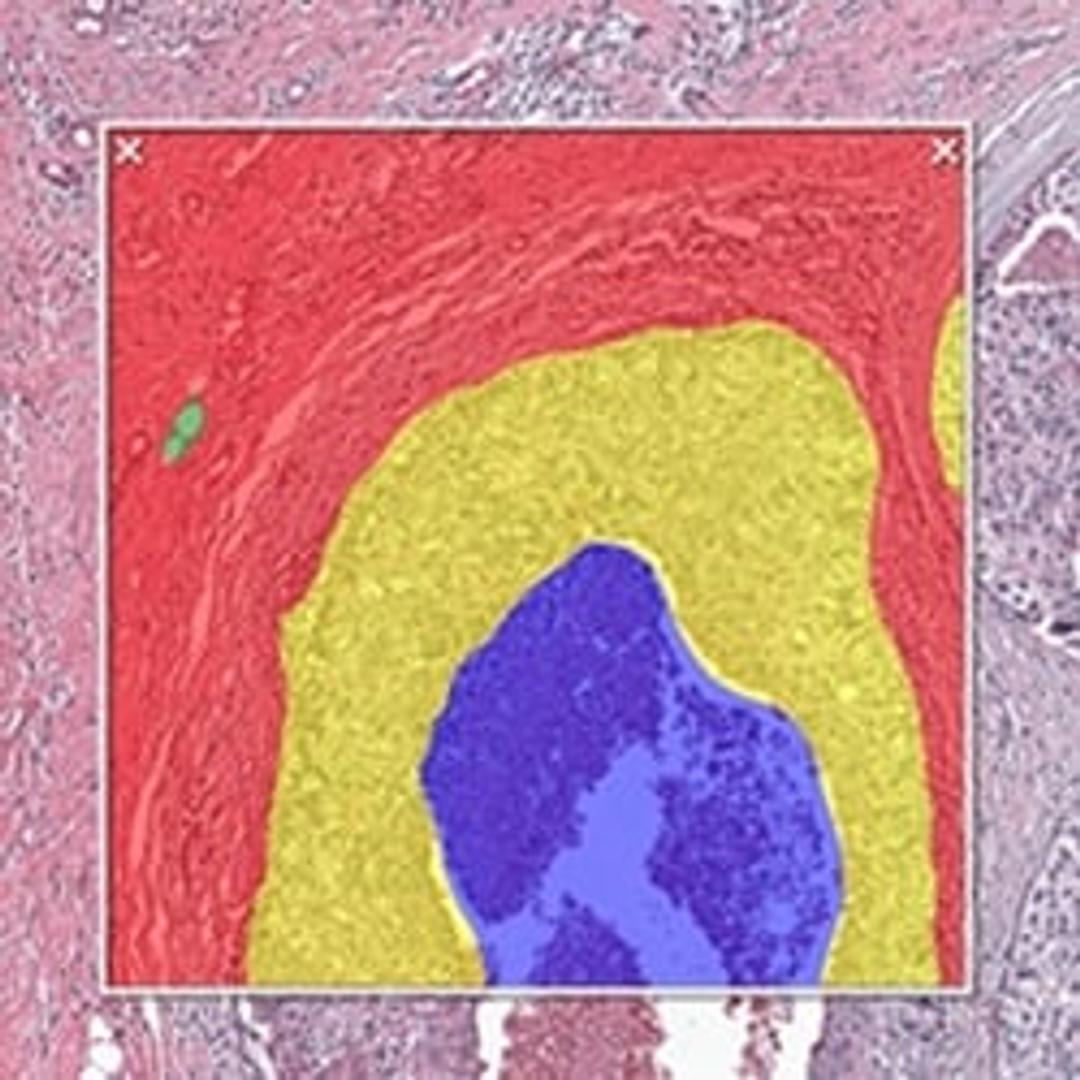

HALO AI is a collection of train-by-example classification and segmentation tools underpinned by advanced deep learning neural network algorithms. HALO AI classifiers can be trained to quantify tissue classes, to segment tissue classes for analysis with other HALO image analysis modules, to find rare events or cells in tissues, and to categorize cell populations into specific phenotypes.

POWERFUL TISSUE SEGMENTATION

HALO AI now includes the option of three powerful neural networks – VGG, DenseNet and MiniNet. VGG, a well-known and more traditional network, was used to build the Indica Labs submission in the CAMELYON17 challenge and was the first neural network integrated with HALO AI. DenseNet is a more modern network capable of creating more robust classifiers at higher resolution compared to VGG. MiniNet, a custom network developed at Indica Labs, is more shallow than VGG or DenseNet, but can produce a solution quickly with limited training data and is therefore useful for testing new AI applications.

EXCEPTIONAL CELL CLASSIFICATION

Segment nuclei with the new Segmentation classifier. Utilize HALO AI’s pretrained networks for H&E, single IHC, or DAPI stained images for an out of the box solution. Or train your own nuclei segmentation network for a specific application (unique tissue or advanced staining protocols). Once nuclei are segmented, take it a step further using the Nuclei Phenotyper classifier to automatically assign cells into user defined phenotypes with a few quick training examples.